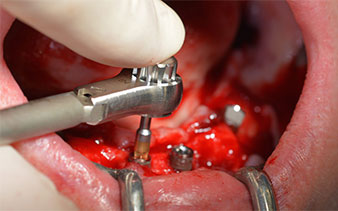

The mental foramen was first identified as a limiting anatomical structure and then the cortical bone of the crest was smoothed with the straight handpiece and a large rose-head bur (Fig. 4).

This corresponds to the next preset position in the Implantmed. Here we see the W&H contra-angle handpiece being held at a 45° angle to mesiocaudal in the region of 45 in order to preserve the mental nerve. The mental foramen is used as the anatomic reference for all drilling in this region. The subsequent holes were drilled at a reduced speed of 300 rpm (Fig. 10 and 11).

The next programmed setting is already for placement of the implants. In our practice we usually employ a torque of 32 Ncm to place the implants (Fig. 12 and 13).

High primary stability is an absolute requirement for an immediate restoration. In order to achieve this, the hole was not tapped in this case. The W&H Implantmed drill unit used here is equipped with a suitable special mode for this, which can also be directly selected and is indispensable for many indications. The final revolutions when placing the implants exceeded the value of 32 Ncm and were performed by hand. In such cases, we recommend utilizing the implants’ self-tapping function and twisting the implants backwards and forwards several times. This allows the implant to approach the final position gradually without exerting excessive pressure on the bone (Fig. 14).

Angled abutments (35°) were screwed in to compensate for the divergence of the distal implants, with the result that the emergence profile of all implants was as perpendicular as possible to the bite plane. This is a prerequisite for occlusal placement of the provisional and subsequently the permanent denture (Fig. 15 and 16).